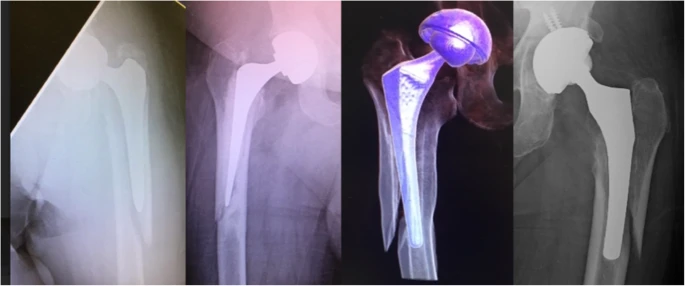

Dans une analyse radiographique d'un grand nombre de fractures périprothétiques, l'équipe de recherche a observé un schéma de fracture non décrit auparavant dans la littérature.La fracture provient du calcar médial passant par le cortex latéral, laissant le cortex médial intact.Ce type de fracture s'appelle une fracture à clapet 'inverse', que l'étude considère comme une fracture commune de Vancouver B2.

Ce nom a été choisi pour deux raisons : premièrement, il s'agit d'une image miroir du 'flip', et deuxièmement, il se comporte comme une fracture fémorale proximale oblique inversée, avec un déplacement supralatéral similaire de l'abducteur tirant le fragment proximal.Des fractures similaires se sont produites avec des tiges cimentées et non cimentées (Figure 2).